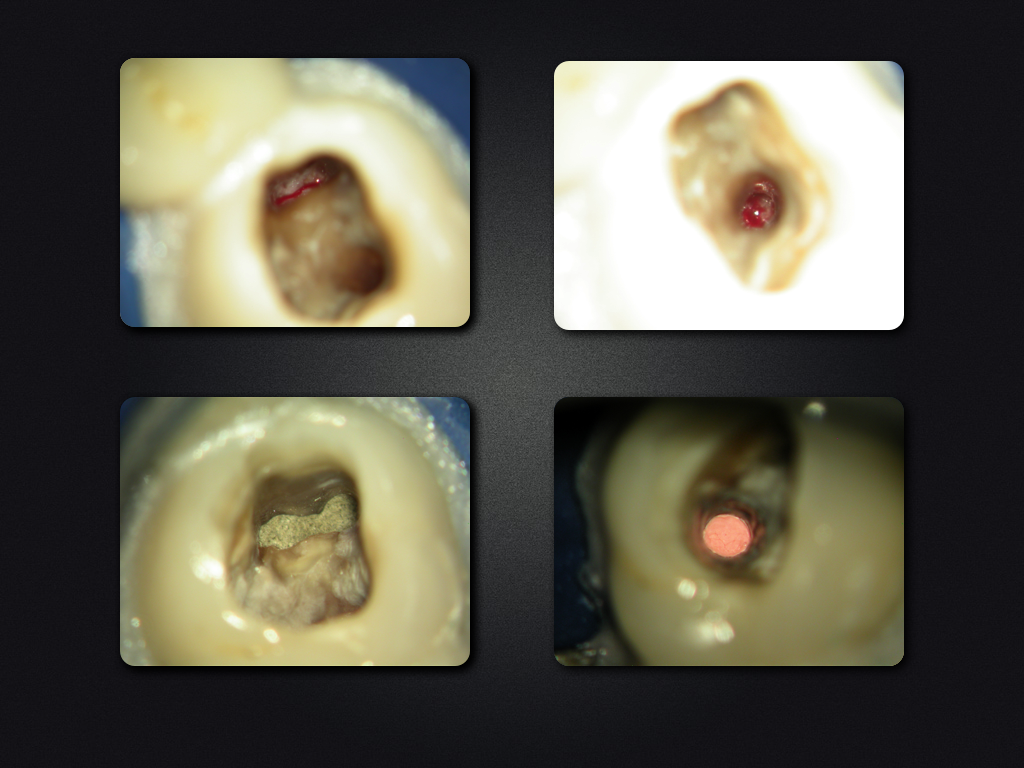

Saving Hopeless Teeth (XXXII)